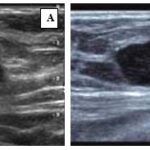

Anexo 2. Imágenes ecográficas del CMTN

Características ecográficas del CMTN

Los resultados de las características ecográficas revelan los siguientes hallazgos en la investigación. Se describe la forma del nódulo de la siguiente manera: en su mayoría es ovalado (n = 13,76%), con márgenes microlobulados (n = 7, lo que corresponde al 41%), seguido de márgenes circunscritos (n = 5, equivalente al 29%). Además, se observa que son hipoecoicos (n = 16, lo que corresponde al 94,2%) y se ubican de manera paralela al eje cutáneo (n = 15, equivalente al 88,2%).

En relación con los hallazgos acústicos posteriores, se destaca que 14 pacientes, que conforman el 82% del grupo, no presentaban hallazgos acústicos ni calcificaciones intra ni extra nodulares.

En cuanto a la vascularización, se observa que en 14 pacientes (equivalente al 82%) no se detectó vascularización en el estudio realizado con Power Doppler. En contraste, 3 pacientes presentaban vascularización periférica, representando el 17,6% de la muestra. En ninguno de los casos se informó distorsión arquitectural ni cambios cutáneos. Sin embargo, en 15 pacientes se observaron adenopatías axilares, lo que corresponde al 88,2% del grupo estudiado.

Los hallazgos radiológicos, tanto en mamografía como en ecografía, describen características comunes de los nódulos en pacientes con CMTN, incluyendo la forma ovalada, los márgenes circunscritos o lobulados, la hipoecogenicidad y la ausencia de hallazgos acústicos posteriores. Estos resultados subrayan la importancia de la evaluación exhaustiva de las características mamográficas y ecográficas en el diagnóstico y la estratificación de los CMTN, que presentan concordancia con lo descrito en la bibliografía médica actual revisada.

Los hallazgos imagenológicos en mamografías, ecografías y resonancias magnéticas en pacientes con CMTN concuerdan con la bibliografía médica actual, lo que respalda la utilidad de estas técnicas para el diagnóstico y caracterización de los CMTN.